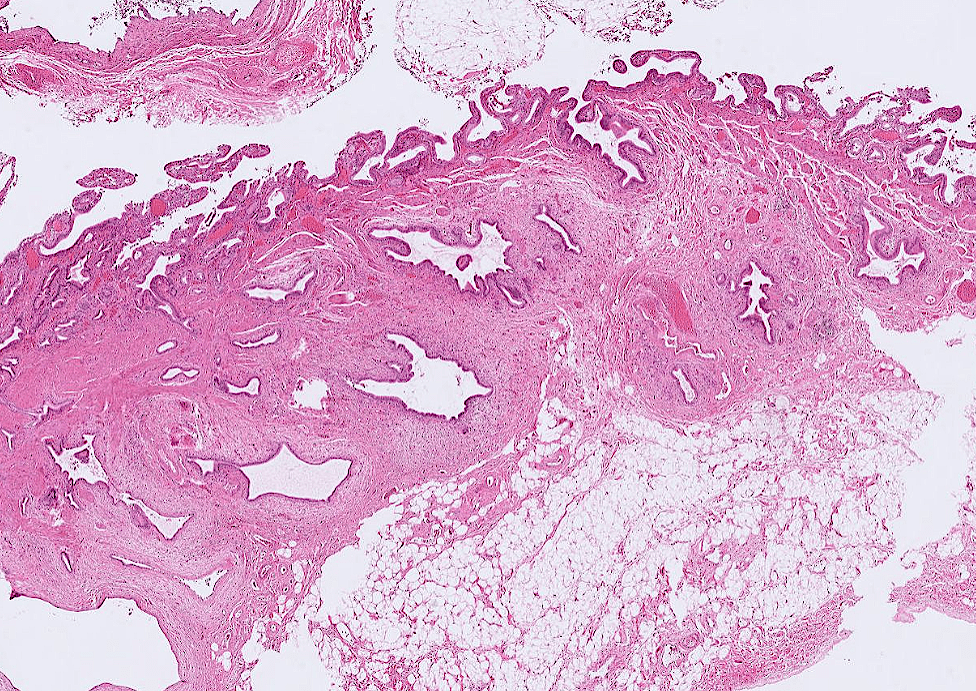

lung adenocarcinoma

colon cancer

endometrial cancer